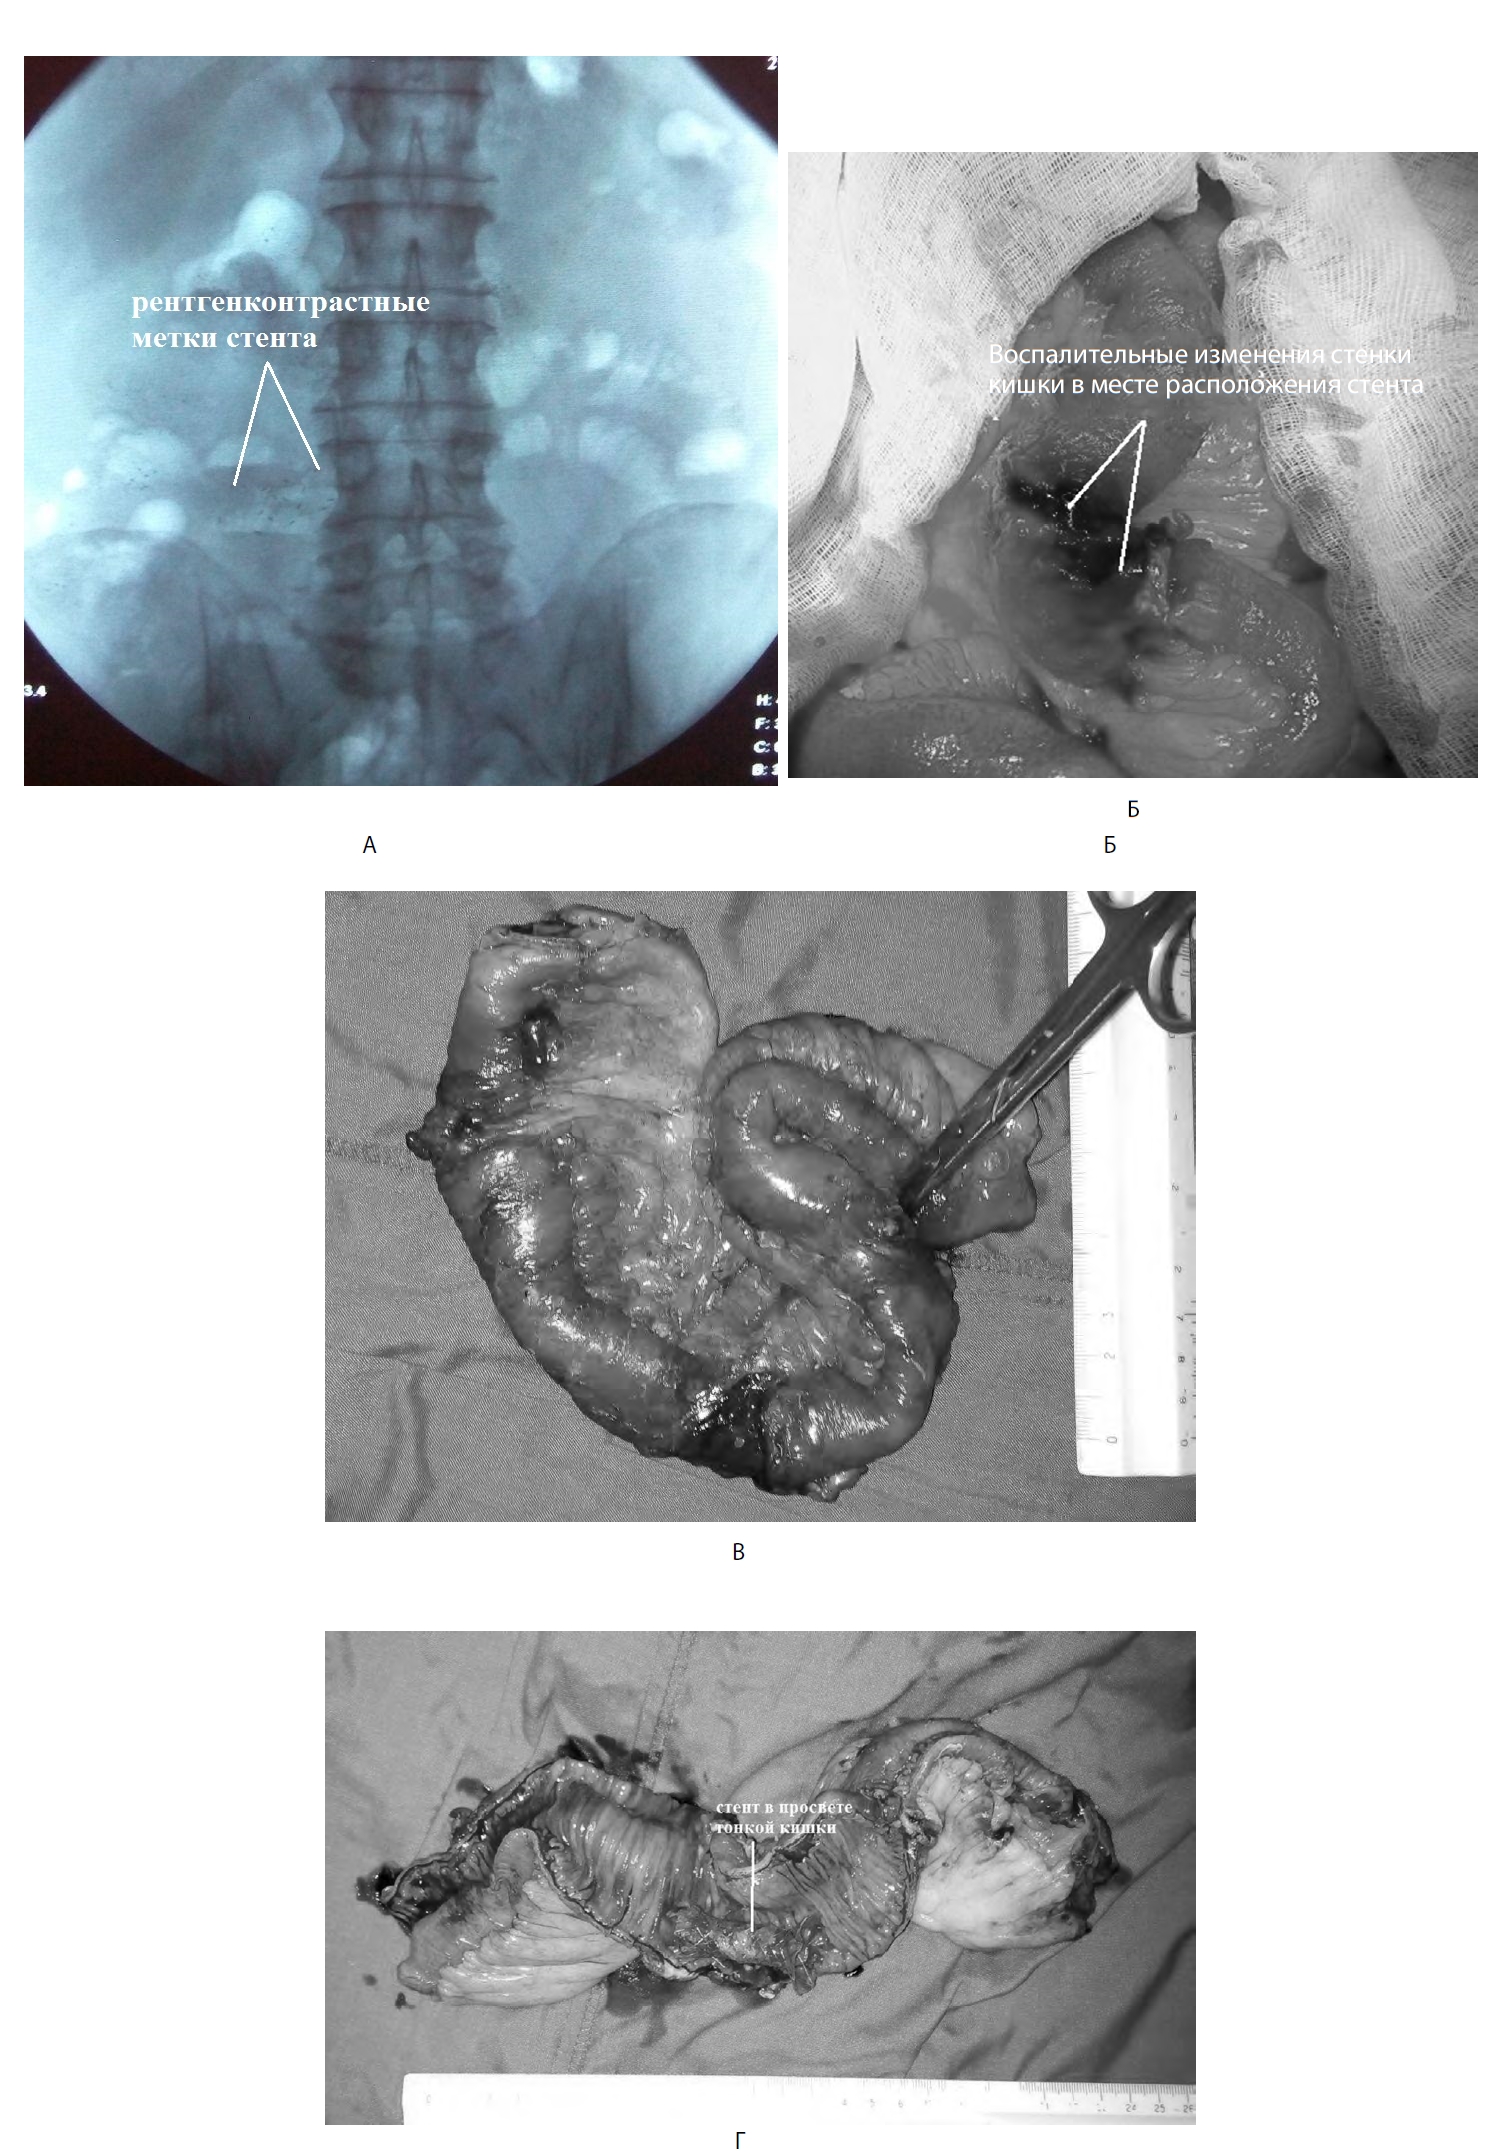

В результате проведенных оперативных вмешательств и лечебных манипуляций наблюдалась положительная динамика в состоянии больного. На фоне отсутствия жалоб, нормализации температуры тела и лабораторных показателей, отсутствия отделяемого по дренажам, полного регресса жидкостных образований в брюшной полости, а также воспалительных изменений в парапанкреатической клетчатке по данным УЗИ и КТ 15.12.2017 г. при рентгенографии органов брюшной полости выявлена миграция стента в тонкую кишку на расстояние около 100 см от связки Трейца (рис. 13 А).

Рис. 13. Этапы операции по удалению стента из просвета тонкой кишки (91-е сут болезни). А — рентгенограмма органов брюшной полости, на которой в проекции тонкой кишки определяется стент; Б — воспалительный инфильтрат и петля тонкой кишки в месте расположения стента; В — макропрепарат удаленной петли тонкой кишки; Г — удаленный участок тонкой кишки на разрезе, в просвете цистогастральный стент

С учетом отсутствия клинической картины кишечной непроходимости было принято решение о динамическом наблюдении за больным с ежедневными рентгеновскими исследованиями живота. В течение 5 сут продвижения стента по кишке не отмечалось. В связи с неизменным положением инородного тела больному показано оперативное лечение. 21.12.2017 г. выполнена лапароскопия, при которой выявлен выраженный спаечный процесс в верхнем этаже брюшной полости, конгломерат петель тонкой кишки вокруг дренажной трубки, установленной в полость абсцесса брыжейки тонкой кишки. При интраоперационной ревизии и рентгеноскопическом контроле установлено, что стент находится в одной из петель тонкой кишки, вовлеченных в спаечный конгломерат вокруг дренажа абсцесса корня брыжейки тонкой кишки. Разделение спаек лапароскопическим способом не представлялось возможным, в связи с чем была выполнена лапаротомия. При разделении спаек и мобилизации петель тонкой кишки выявлено, что стент фиксирован к воспалительно-измененным стенкам кишки. Выполнена резекция участка тощей кишки с инородным телом с наложением анастомоза конец в конец (рис. 12 Б–Г).